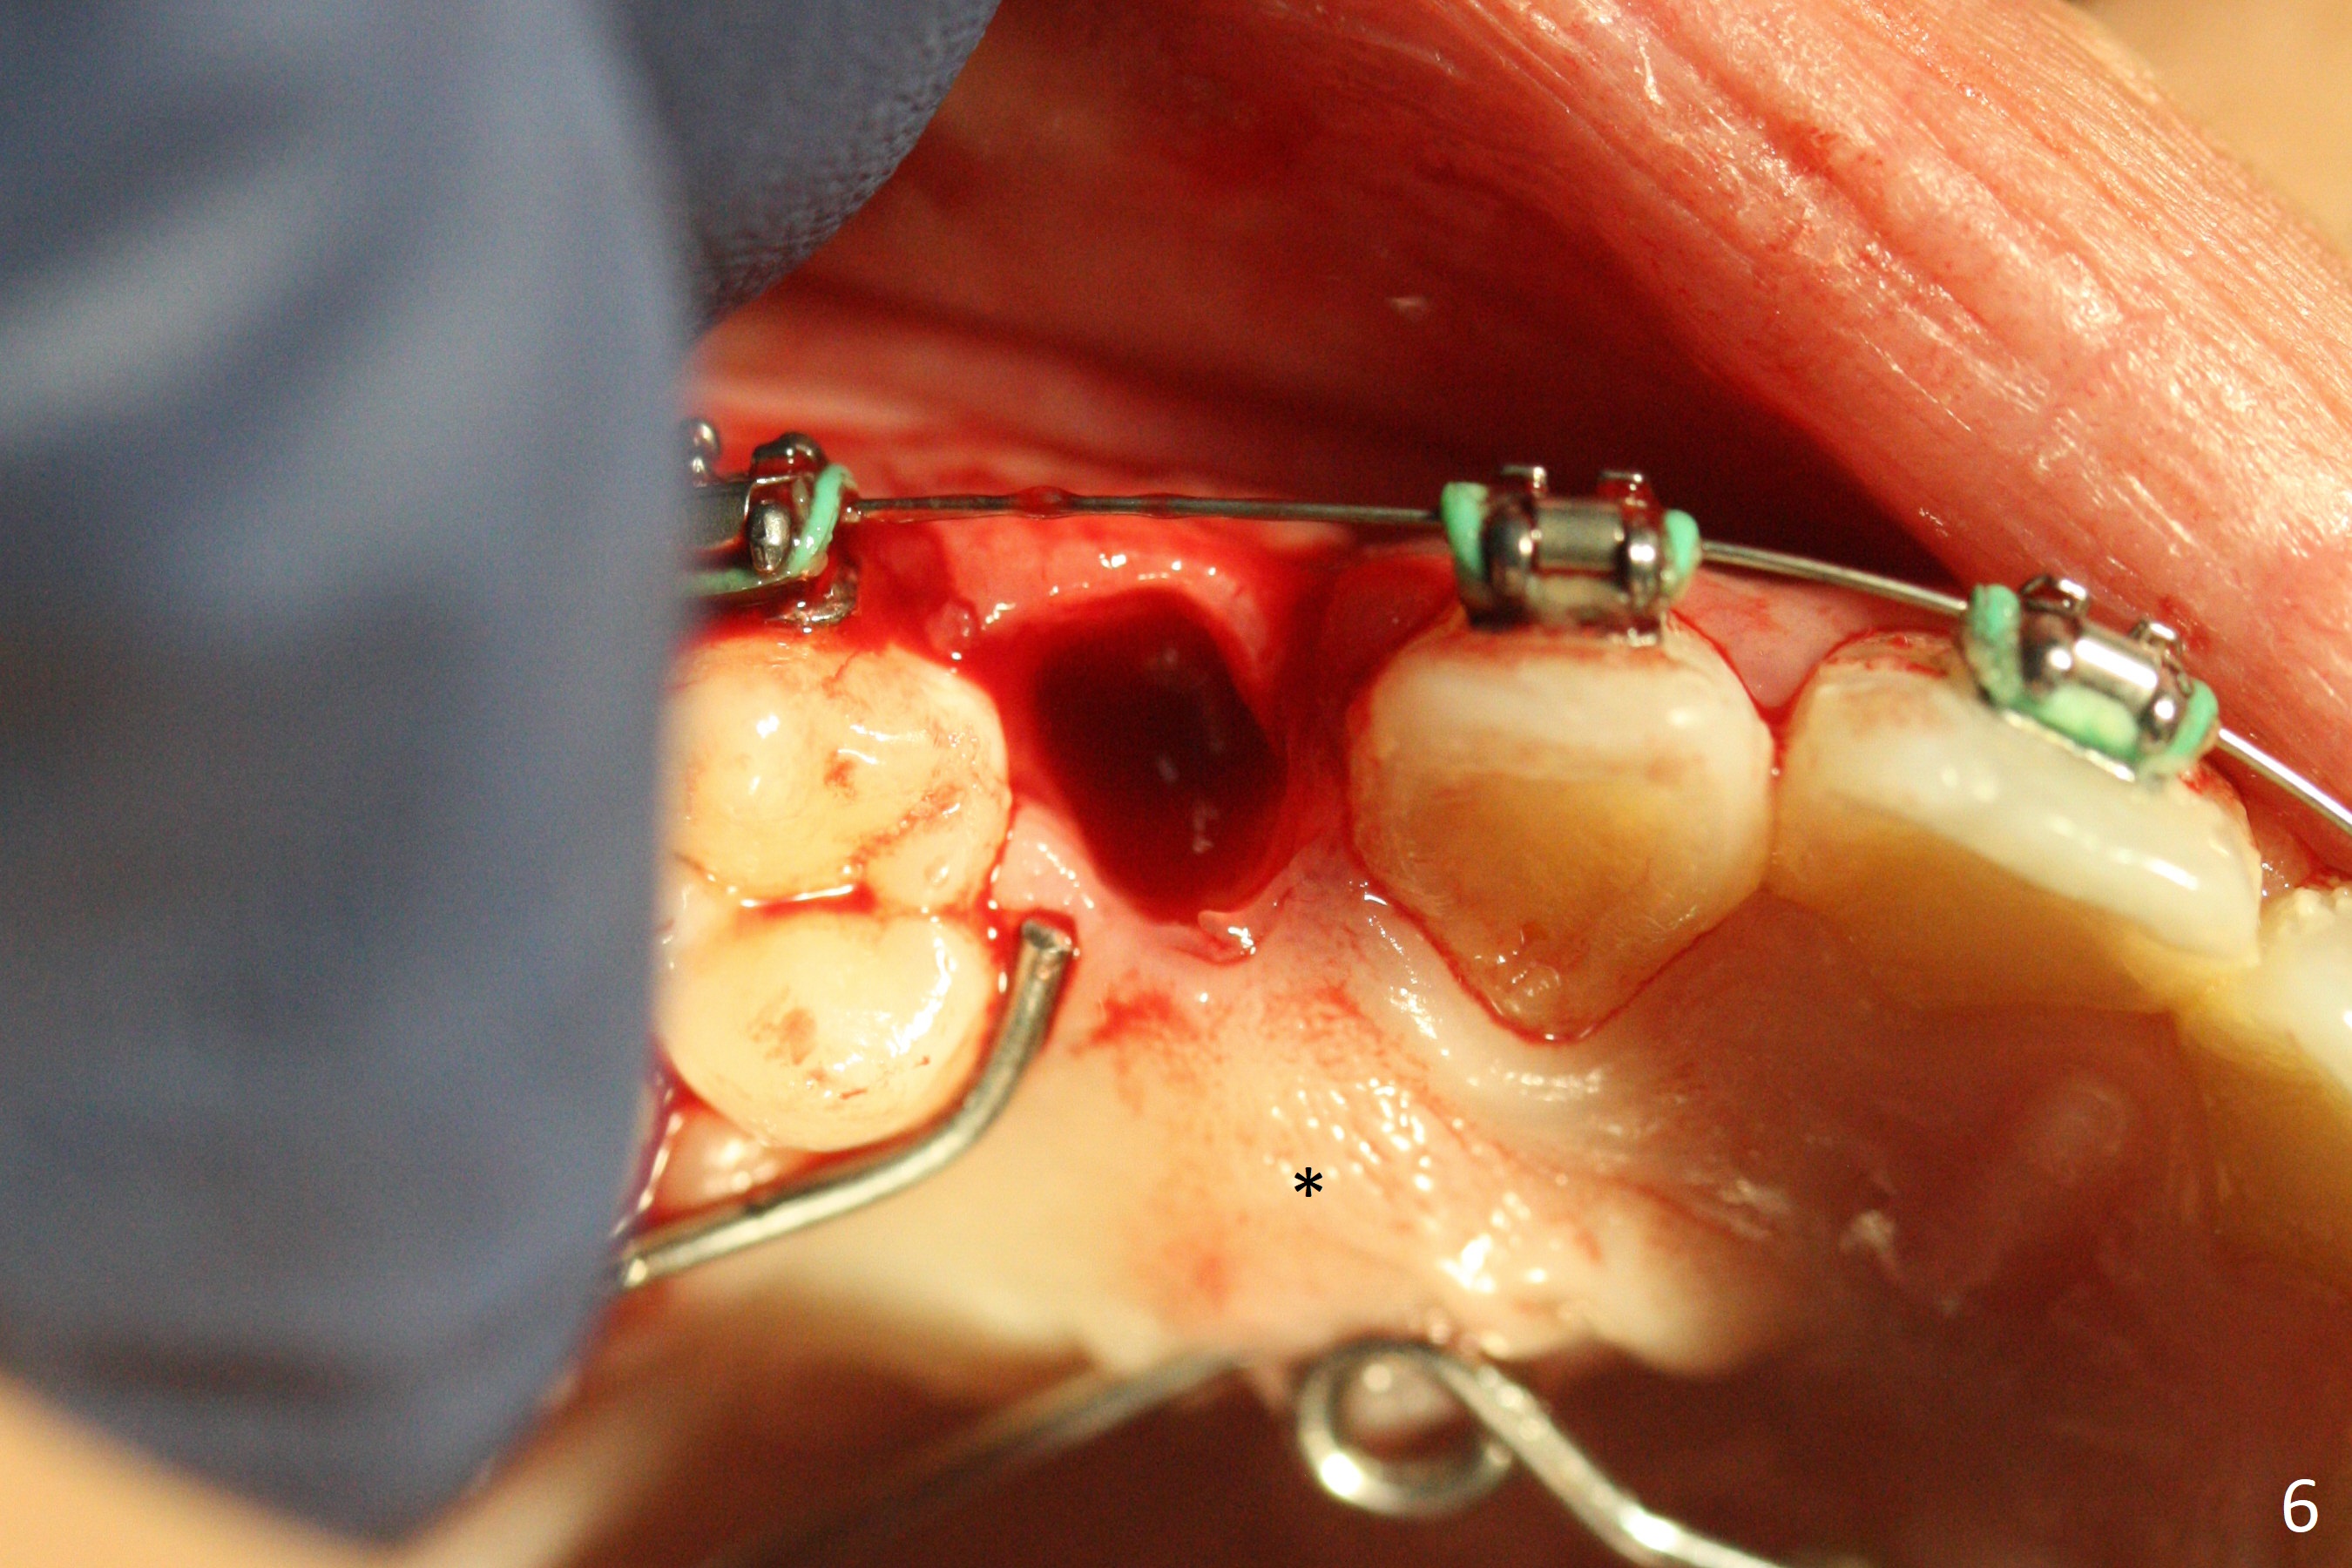

A 13-year-old woman has an impacted canine (Fig.1 (6)) and retained deciduous one (C). After initiation of orthodontics, she returns for surgical access to the impacted canine and placement of device to facilitate eruption (Fig.2,3). Incision is made buccal (Fig.4), but there is no tooth buccal (Fig.5). Extraction of the deciduous canine does not reveal the impacted one (Fig.6), but there is palatal elevation (*). Palatal access shows the impacted tooth (Fig.7) and allows placement of a retraction device (Fig.8). Careful clinical exam and CBCT are necessary diagnostic steps.